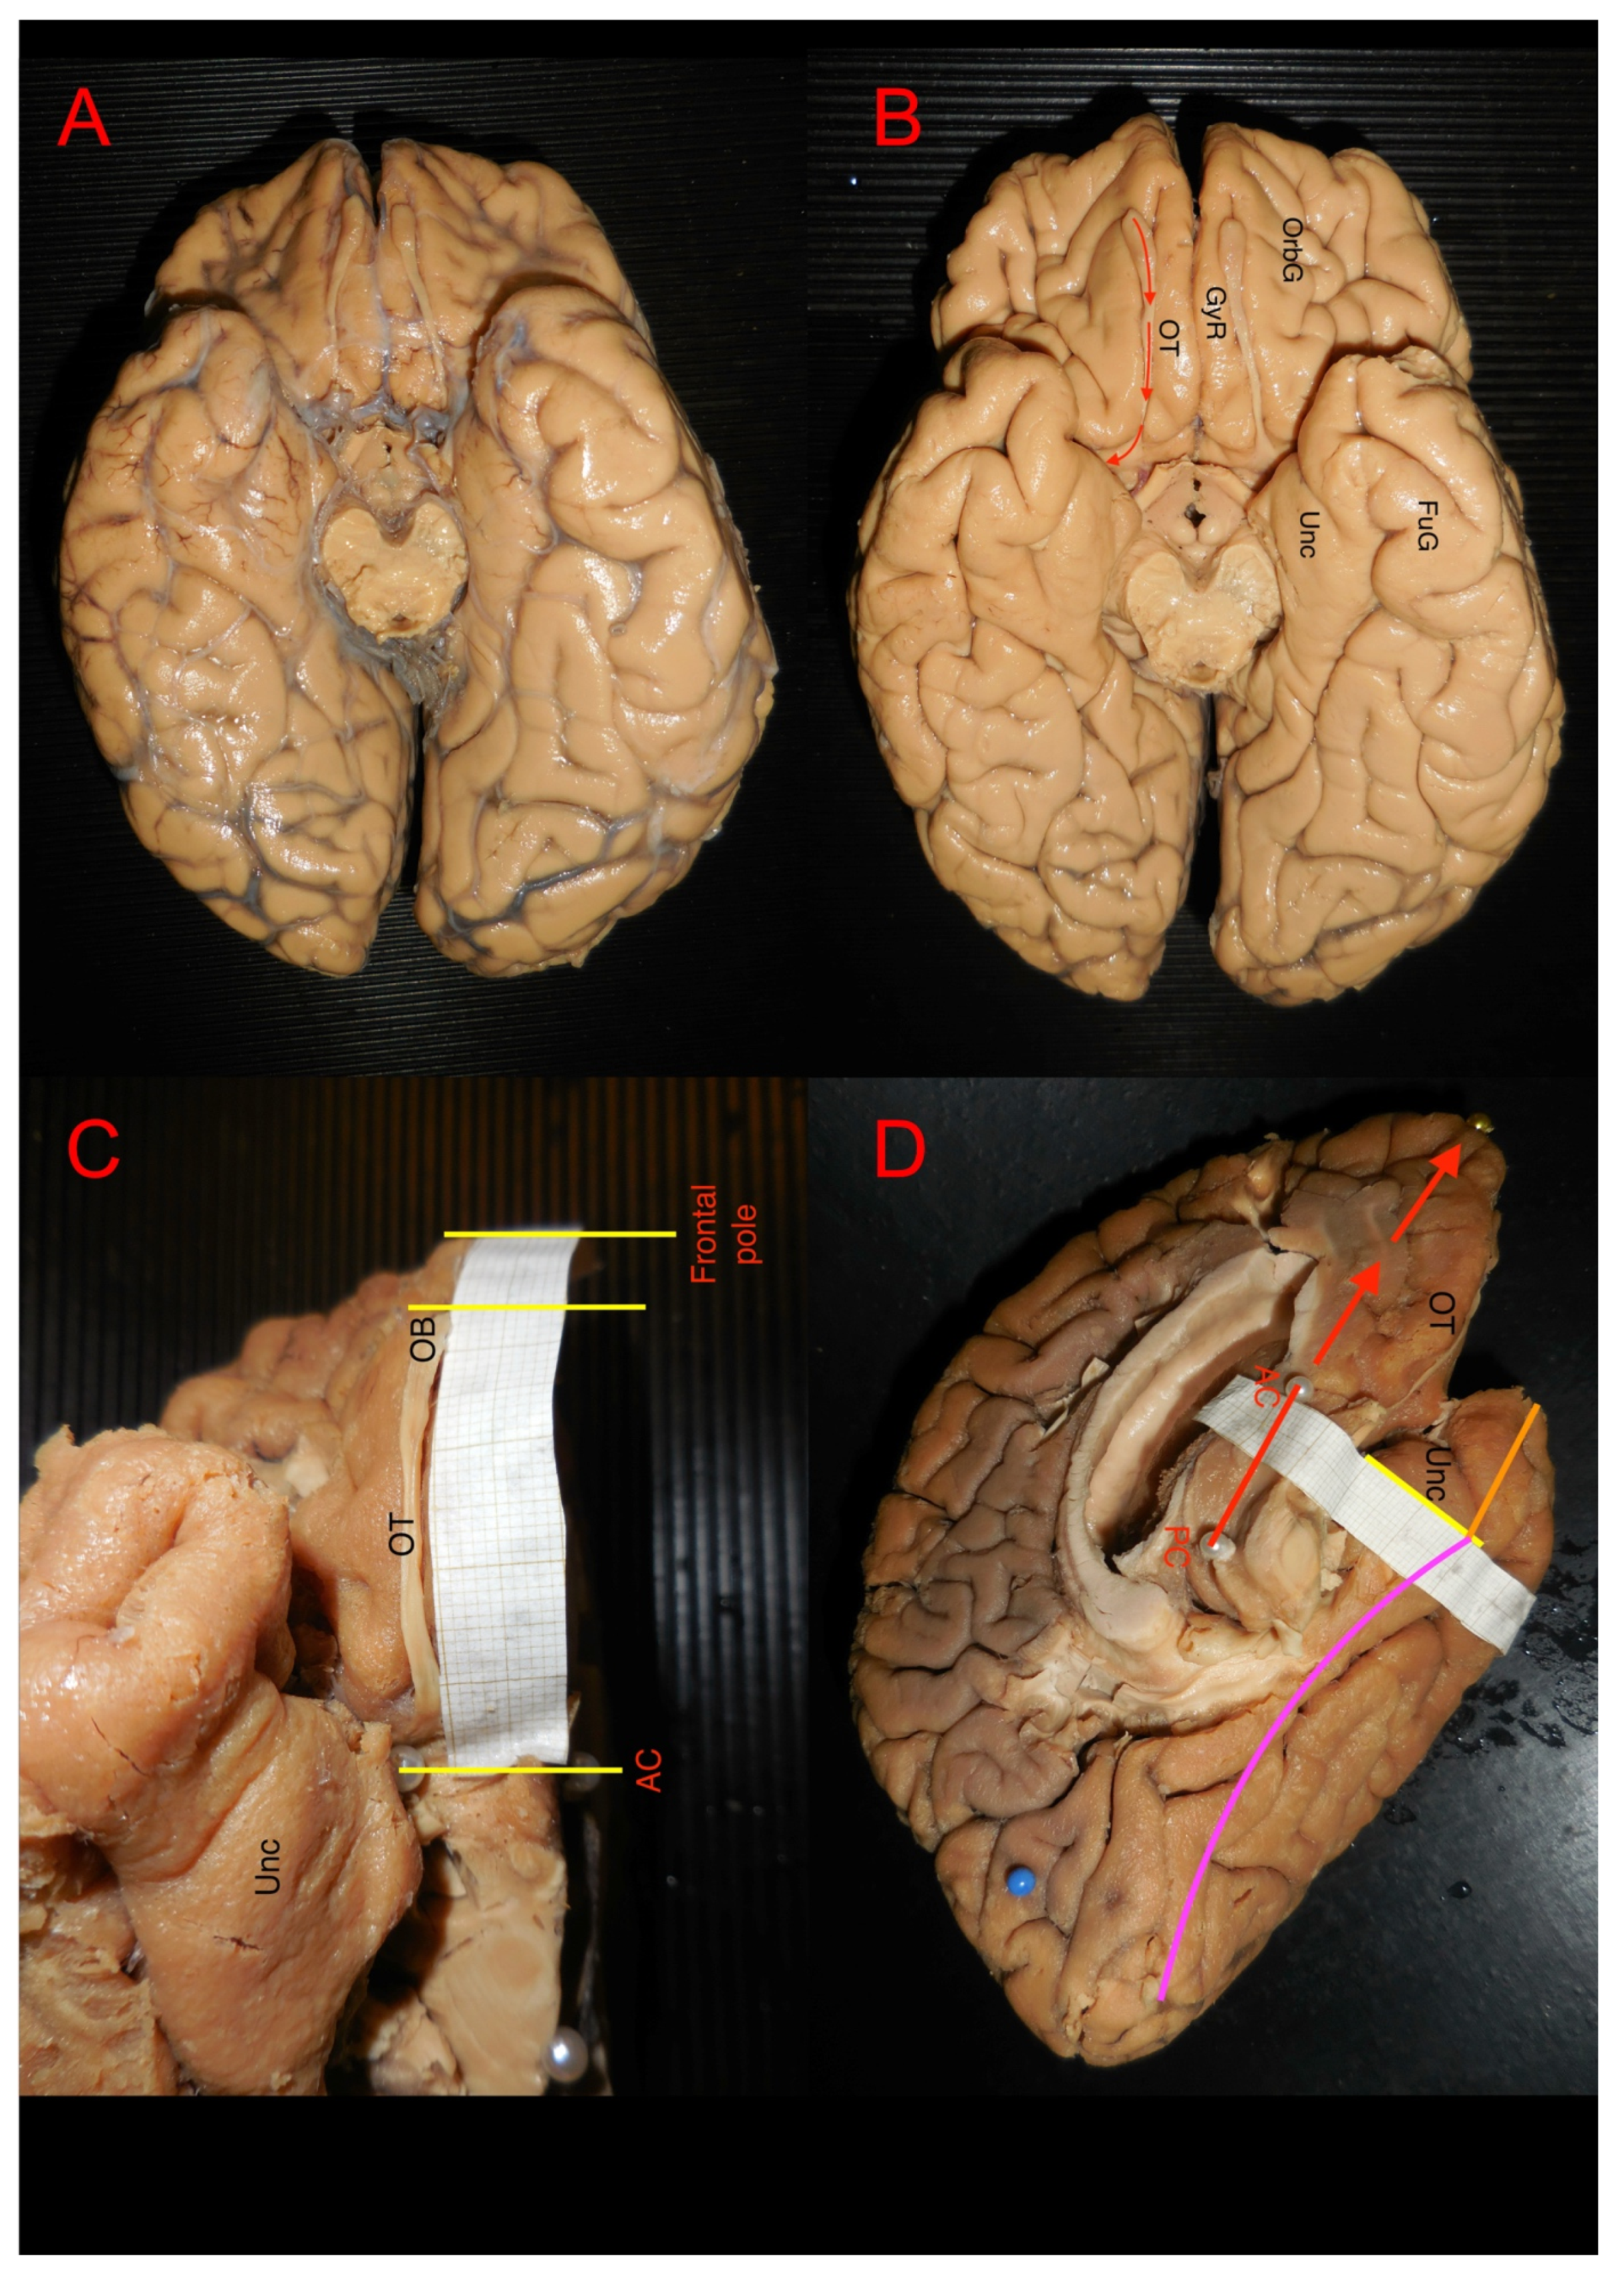

3.1. Ex Vivo Measurement of White Matter Structures

3.2. Ex Vivo White Matter Dissection and Analysis